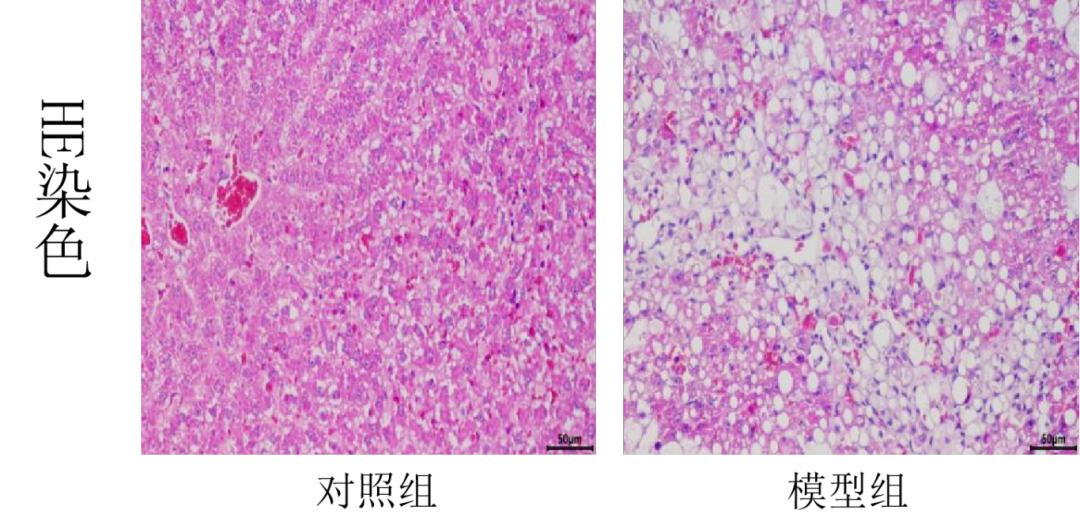

3.肝脏病理

对照组肝脏结构正常。模型组肝脏出现大量脂质空泡,肝细胞气球样变及炎性细胞浸润,较对照组有极显著病理损伤(p<0.001),且模型组肝脏纤维化程度高于(p<0.05)对照组,油脂小体体积大且密集。模型+辛伐他汀组脂质空泡少,肝细胞气球样变及炎性细胞浸润有所改善,病理损伤程度显著与模型组差异非常显著(p<0.01),且纤维化程度显著轻于(p<0.05)模型组,油脂小体体积和密度小于模型组。

肝细胞脂肪样变(黄色箭头)肝细胞气球样变(蓝色箭头)炎性细胞浸润(黑色箭头)